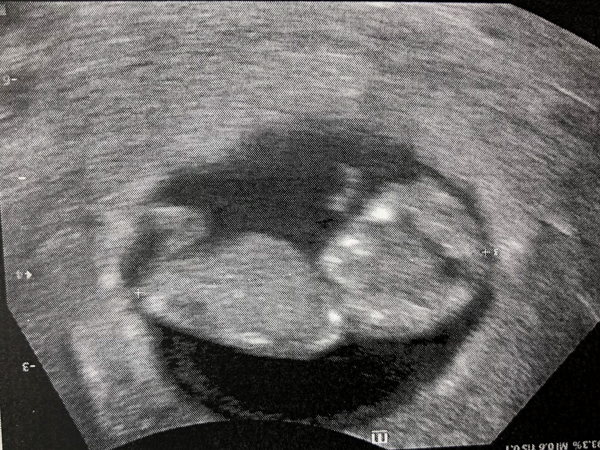

Little baby at 10 weeks!

We had ultrasounds at 6 and 10 weeks that showed a healthy baby and genetic testing (because I am now an old lady aka “advanced maternal age” and it was covered by insurance) and that’s how we found out the sex. We had the doctor write “boy” or “girl” and put it in an envelope and took it to Sarah Cramer’s studio. After Mazen and I had had so much fun with confetti there a few years ago, I knew confetti was the perfect gender reveal! I bought these cannons online and we arrived with both pink and blue. Sarah opened the envelope and handed us the appropriate color. It was such a wonderful way to find out! I honestly did not care if we had a boy or girl since I would be equally as excited to have a brother for Mazen and re-use all of my boy stuff and to try out all the new stuff with a girl. But Thomas and Mazen were both on Team Boy, so when the confetti came out blue, we were all thrilled. I’m happy that they are so happy!

So, he said a prayer and for the next few weeks we would listen to my tummy to see if anything was happening. He told me in the gym locker room that my tummy was in fact growing (thanks Mazen!) And so it didn’t come as too much of a surprise when we presented him with the ultrasound pictures the morning we left for Bald Head and said, “We went to the doctor so he could look inside and there IS a baby in there!” He seemed plenty excited. Since then he’s been talking about his “baby brother” a lot and has been collecting trinkets to give to him when he comes (a free fidget spinner pen being the most recent gift)!

I had the ultrasound photo tucked in between them so when she lifted out the Peeps she saw it and jumped a mile into the air!